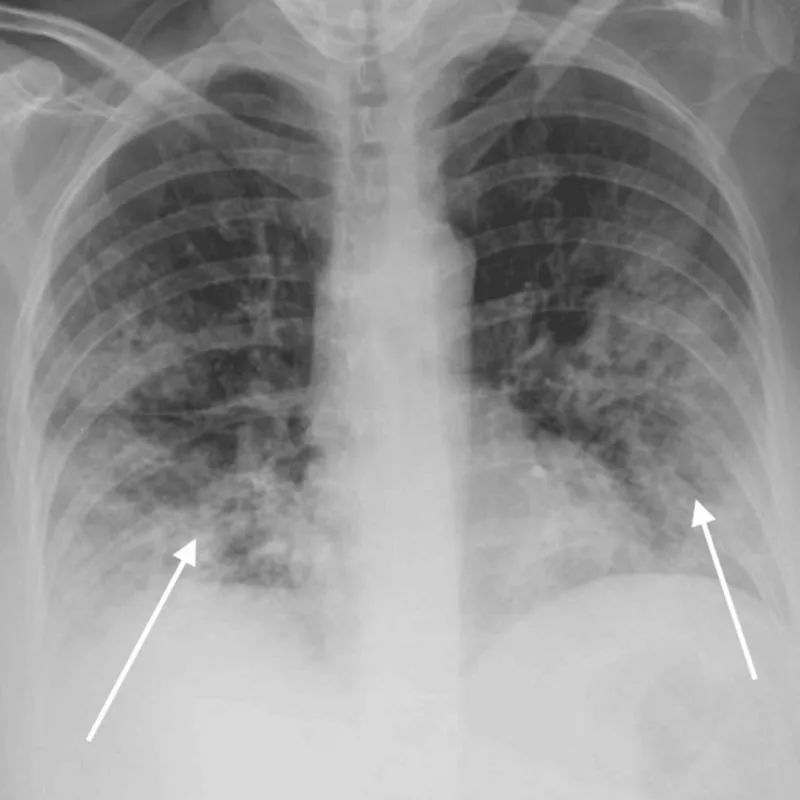

- 儿童/青少年耐多药结核病,诊断和治疗要点看这里! 儿童结核病的诊断面临许多挑战,包括非特异性体征和症状、细菌载量低以及难以收集足够的样本等。……